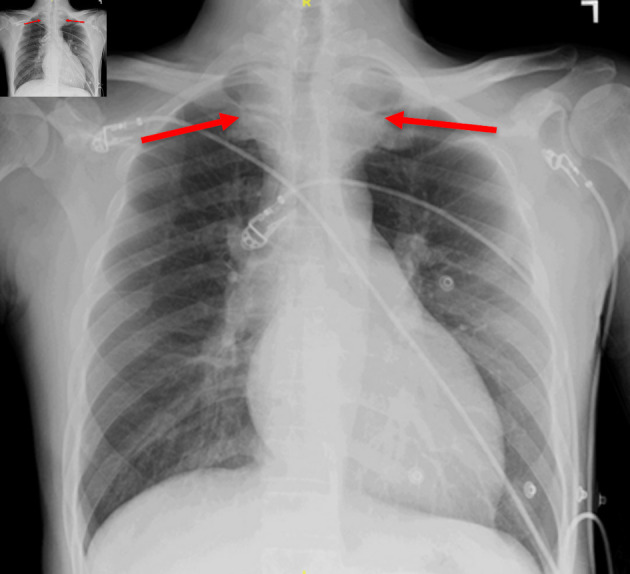

Thyrotoxicosis has been associated with several cardiac conditions including atrial fibrillation, congestive heart failure due to left ventricular dysfunction, and cardiomyopathy. However, few cases of ventricular fibrillation as a complication of thyrotoxicosis have been reported. Our case described a 45-year-old male with a history of hypertension and Graves' disease, who presented with 1 week of left-sided chest pain associated with shortness of breath on exertion and occasional palpitations. His workup revealed acute diastolic congestive heart failure secondary to thyrotoxicosis, causing pulmonary hypertension, which led to ventricular fibrillation and cardiac arrest. After being treated with methimazole and metoprolol, the patient's symptoms improved. This case underscores the significance of assertive medical interventions alongside both invasive and non-invasive cardiac procedures. Addressing thyrotoxicosis and ventricular arrhythmia in hyperthyroid patients is crucial to prevent potentially life-threatening complications.